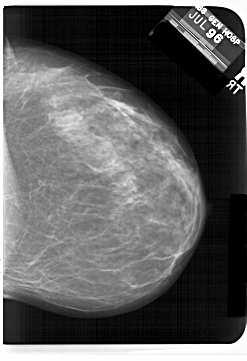

A_1408_1.RIGHT_MLO

RIGHT_CC LINES 6841 PIXELS_PER_LINE 4681 BITS_PER_PIXEL 12 RESOLUTION 43.5 NON_OVERLAY